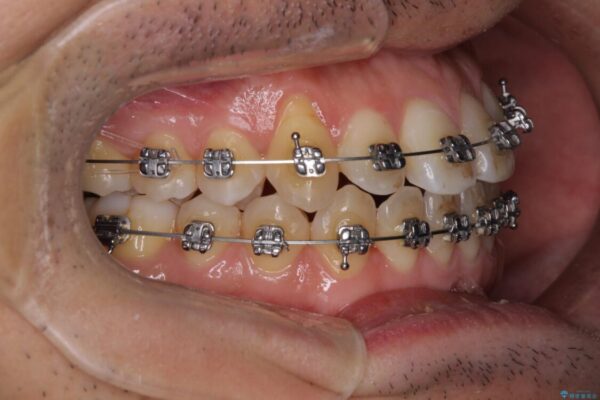

治療途中

• 左右の八重歯が気になる ワイヤー装置での咬み合わせ改善 治療途中画像